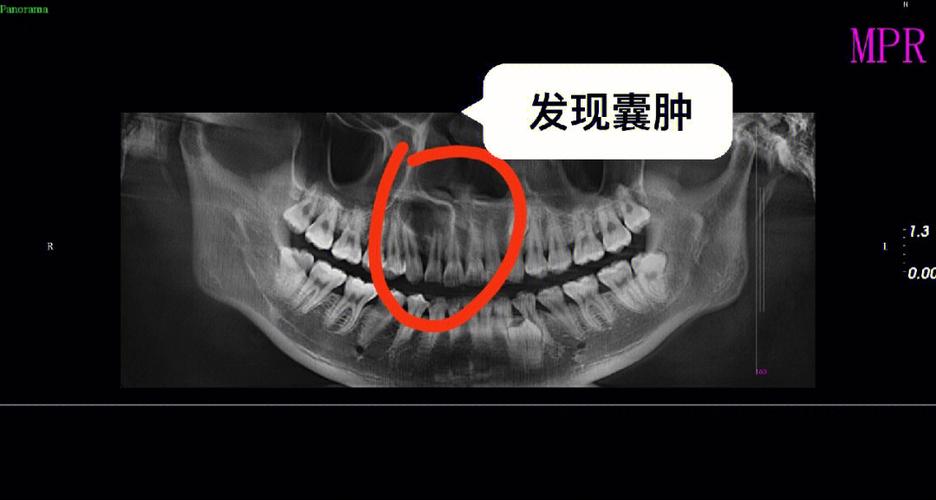

- 囊腔是否被骨组织逐渐填充(骨愈合)。

- 根尖周病变是否消失。

- 有无复发迹象。